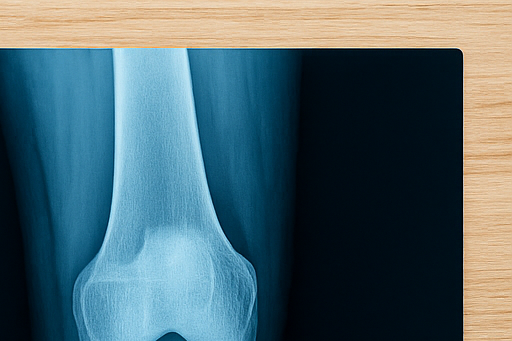

골절은 단순히 뼈가 부러진다는 의미를 넘어, 회복 과정에서 생활 습관과 식습관까지 큰 영향을 받습니다.

특히 피로골절이나 운동 중 발생하는 골절은 치료와 재활에 시간이 오래 걸리기 때문에 음식 선택이 중요합니다.

이번 글에서는 골절 회복에 도움이 되는 음식 10가지와 반드시 피해야 할 음식 5가지를 정리해, 뼈 건강을 빠르게 되찾고 재활 과정에서 놓치기 쉬운 영양 관리까지 함께 살펴보겠습니다.